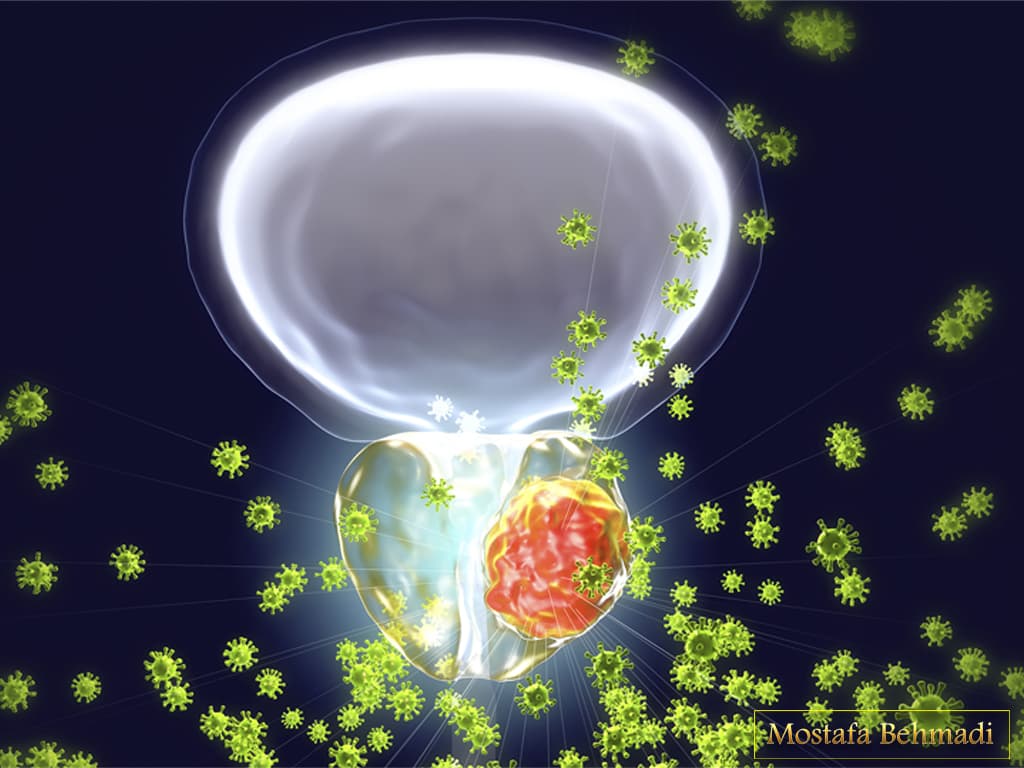

سرطان به تکثیر خارج از کنترل سلول ها گفته می شود. زمانی که سلول های یک بافت بصورت کنترل نشده و خارج از روند عادی شروع به تکثیر می کند. آن بافت به اصطلاح سرطانی می شود. گاهی اوقات این توده ی سرطانی از بافت خود حرکت کرده و در بافت های دیگر نیز ایجاد سرطان می کند. به این امر اصطلاحا متاستاز یا تهاجم گفته می شود. سرطان پروستات شایع ترین و مهم ترین سرطان در بین مردان است به صورتی که دومین عامل مرگ و میر در جهان گزارش شده است.

غده ی پروستات در تولید و ذخیره ی مایع منی نقش دارد و بنابراین علاوه بر مشکلی که در آقایان ایجاد می کند ، می تواند بر روی روابط زناشویی و حفظ خانواده و از نظر اجتماعی نیز اثرگذار باشد.

پروستات غده ای در دستگاه تناسلی مردان است. این غده در لگن زیر مثانه و جلوی راست روده قرار دارد. پروستات در ساخت و ذخیره ی مایع منی نقش دارد. اندازه ی متوسط پروستات مشابه گردو است و اگر این غده بیش از مقدار طبیعی رشد کند و سرطانی شود دفع ادرار را کند می کند چون قسمتی از پیشابراه از غده پروستات می گذرد.

بیماری های جنسی مثل سفلیس ،سوزاک ،هرپس و … می تواند علاوه بر ایجاد عفونت می تواند راهی برای ایجاد سلول های سرطانی در پروستات ایجاد می کند.